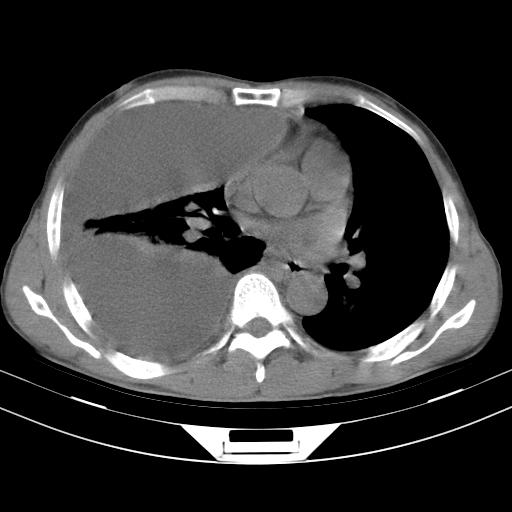

男性,44岁,结核病史多年。现胸闷气短,咳嗽,偶咳血。

1)两肺继发性肺结核伴空洞形成,左肺多发性结核球。2)右侧大量胸腔积液伴右肺部分膨胀不全。3)纵隔淋巴结肿大。

1,双肺多发结节 并空洞影改变, 左侧胸腔积液并部分包裹, 结合原病史首先考虑结核. 但也不除外其它.

2,左侧有一根肋骨陈旧性骨折? 建议追查 .

吉大一院胸水抽检结果:结核性胸水